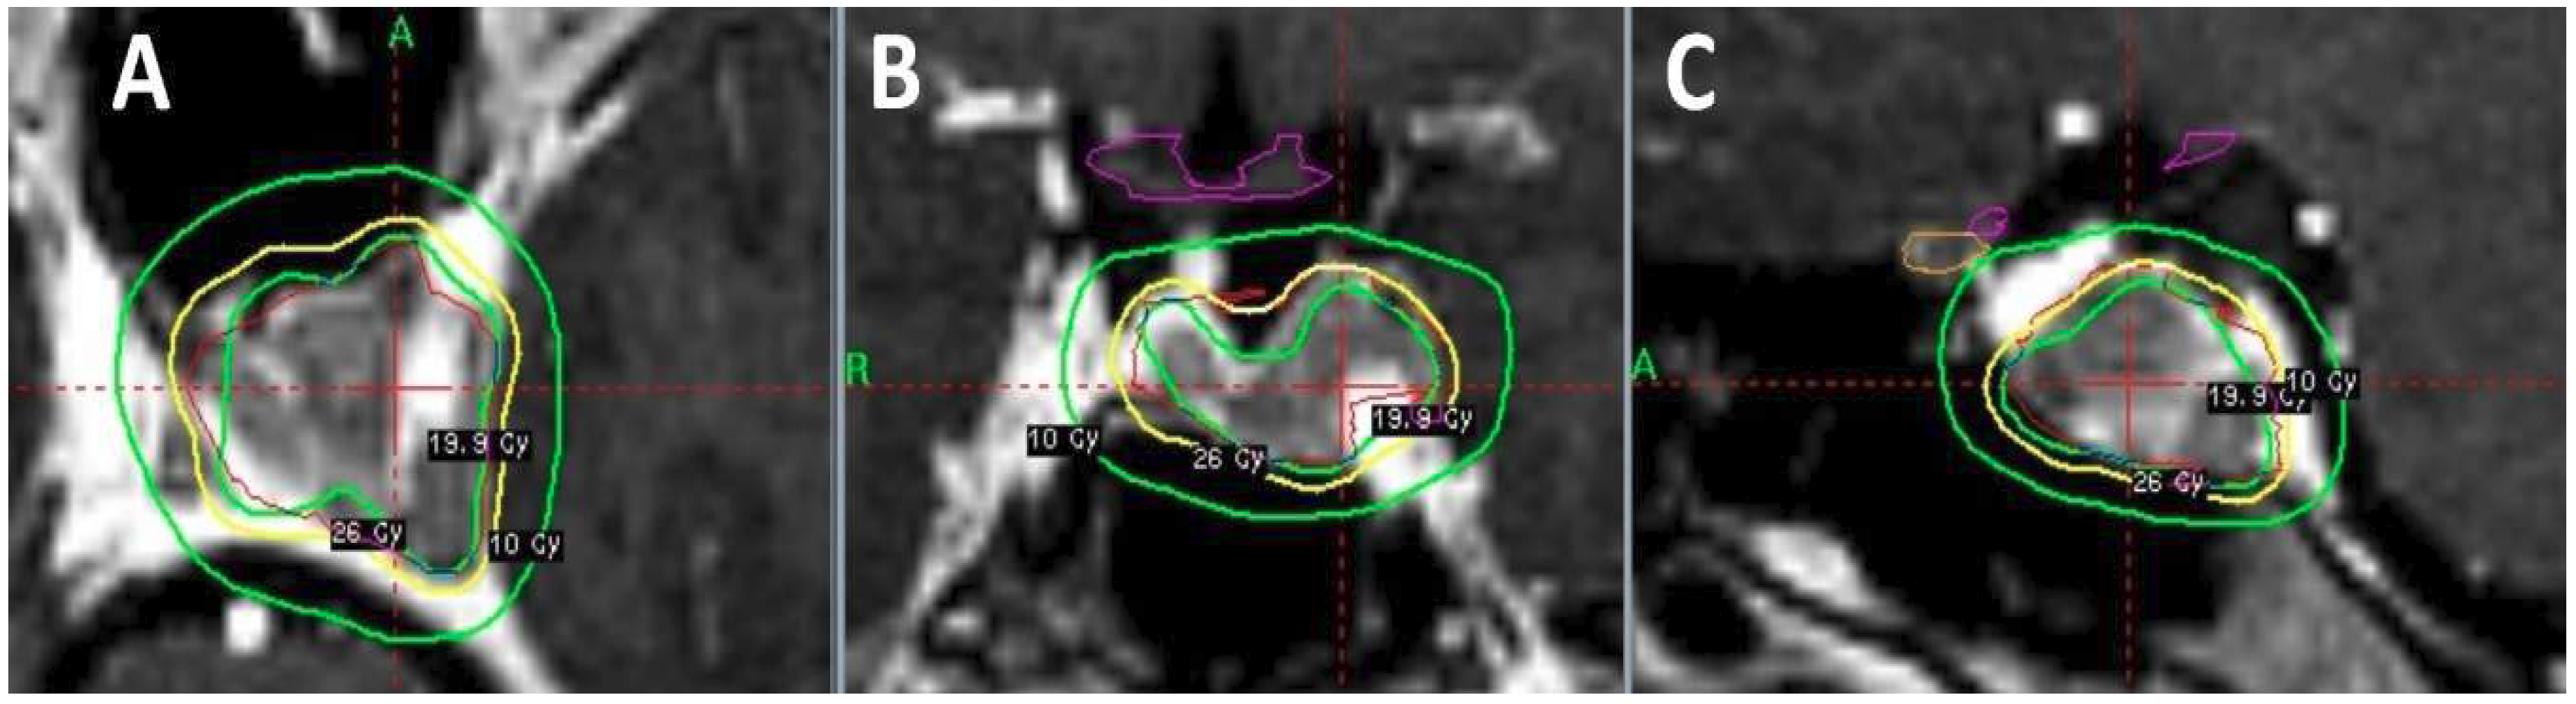

- Beltran, C.; Roca, M.; Merchant, T.E. On the benefits and risks of proton therapy in pediatric craniopharyngioma. Int. J. Radiat. Oncol. Biol. Phys. 2012, 82, e281–287. [Google Scholar] [CrossRef] [PubMed]

- Gunther, J.R.; Sato, M.; Chintagumpala, M.; Ketonen, L.; Jones, J.Y.; Allen, P.K.; Paulino, A.C.; Okcu, M.F.; Su, J.M.; Weinberg, J.; et al. Imaging Changes in Pediatric Intracranial Ependymoma Patients Treated With Proton Beam Radiation Therapy Compared to Intensity Modulated Radiation Therapy. Int. J. Radiat. Oncol. Biol. Phys. 2015, 93, 54–63. [Google Scholar] [CrossRef] [PubMed]